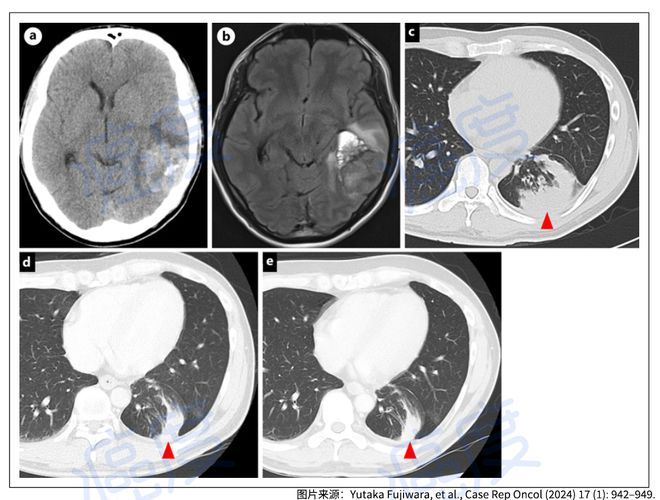

±ØÍþרÖβ»·þ£¡ÂåÀ­ÌæÄáÈ÷ΰ©ÈíÄÔÄ¤×ªÒÆ²¡ÔîÈ«Ïûʧ³¤´ï2Ä꣡(ͼ1)

¡¡¡¡ÕâÊÇÒ»Ãû35ËêÄêÇáÄÐÐÔ£¬ÒòΪͷʹºÍ¸´ÊÓ¶ø¾ÍÕÕâ¸ö»¼ÕßÓÐÎüÑÌÊ·£¬CTÓ°ÏñѧɨÃèºÍºË´Å¹²Õñ³ÉÏñÏÔʾÄÔ²¿Óиö4ÀåÃ׵ĹÂÁ¢ÐÔÄÔÖ×Áö£¬µ¼ÖÂÖÐÏß³öÏÖÁËÒÆÎ»¡£ÁíÍâCT»¹ÏÖÔÚ·Î×óÏÂÒ¶ÓÐÔ­·¢ÐԷΰ©±ØÍþ£¬ÄÔ²¿ÊÖÊõÖ®ºó²¡ÀíÕï¶ÏΪ·ÇСϸ°û·Î°©£¬ÄÔ²¿²¡ÔîÊǴӷβ¿×ªÒƹýÀ´µÄ²¡Ôͨ¹ý·Ö×ÓÕï¶ÏÈ·¶¨ÎªEMA4-ALKÈÚºÏÍ»±ä¡£

±ØÍþרÖβ»·þ£¡ÂåÀ­ÌæÄáÈ÷ΰ©ÈíÄÔÄ¤×ªÒÆ²¡ÔîÈ«Ïûʧ³¤´ï2Ä꣡(ͼ2)

¡¡¡¡»¼ÕßÊ×ÏÈʹÓÿËßòÌæÄáÖÎÁÆÁË2Ä꣬ºóÃæÒòΪ²¡Çé½øÕ¹Ê¹ÓÃÁË1ÄêµÄµÚ¶þ´ú°ÐÏòÒ©°¢À´ÌæÄᣬºóÃæÊ¹ÓÃÁË3ÄêµÄµÚ¶þ´ú°ÐÏòÒ©²¼¸ñÌæÄá¡£ºóÃæËû³öÏÖÁËÈíÄÔÄ¤×ªÒÆ£¨ºË´Å¹²Õñ³ÉÏñ֤ʵ£©²¢°éËæÓи´ÊÓ¡£

¡¡¡¡»¼Õß¿ªÊ¼Ê¹ÓõÚÈý´ú°ÐÏòÒ©ÂåÀ­ÌæÄᣬÿÌì100ºÁ¿ËµÄ¼Ç¼ÒýÆðÁ˲»Á¼ÐÄÀíʼþ£¬°üÀ¨³Õ´ôºÍÇéÐ÷¸Ä±ä£¬°üÀ¨ÒÖÓôºÍÒâÄî¡£»¼ÕßÏ£Íû¸Ä»ØÀ´°¢À´ÌæÄᣬµ«ÊÇÖØÐÂʹÓð¢À´ÌæÄá3¸öÔÂÖ®ºó±ØÍþ£¬ÈíÄÔÄ¤×ªÒÆÔîÔٴνøÕ¹£¬¾­¹ý×ÐϸµÄ¹²Í¬ÉÌÌֺ;ö²ß£¬Ëû¿ªÊ¼Ã¿ÌìʹÓÃ75ºÁ¿ËµÄÂåÀ­ÌæÄᣬÕâ¸ö¼ÁÁ¿½µµÍ±íÏÖΪ»ù±¾¿ÉÒÔÄÍÊÜ¡£¾¡¹Ü³öÏÖÁËѪ֬Òì³££¬µ«ÊÇÐÄÀíʼþºÍÇéÐ÷¸Ä±äûÓи´·¢£¬»¼Õß¼ÌÐøÊ¹ÓõÚÈý´ú°ÐÏòÒ©ÂåÀ­ÌæÄáÖÎÁÆ2Ä꣬ÈíÄÔÄ¤×ªÒÆÔî±íÏÖΪ³ÖÐøÍêÈ«»º½â£¨ÍêÈ«»º½â¾ÍÊÇÕÒ²»µ½¿ÉÆÀ¹À²¡Ô¡£

±ØÍþרÖβ»·þ£¡ÂåÀ­ÌæÄáÈ÷ΰ©ÈíÄÔÄ¤×ªÒÆ²¡ÔîÈ«Ïûʧ³¤´ï2Ä꣡(ͼ3)